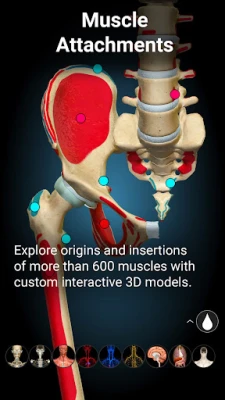

A true and totally 3D app for studying human anatomy, built on an advanced interactive 3D touch interface.

★ You can rotate models to any angles and zoom in and out

★ Muscles

★ Muscles